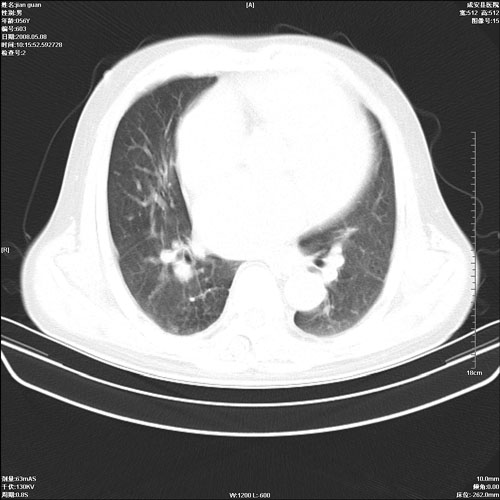

病人 男 60岁 主诉 胸闷 无明显发热 一般情况尚可。

肺结核?

两上肺陈旧性结核;慢支肺气肿、伴感染?

考虑1心功不全,肺水肿

2右上肺结核纤维性病灶、肺气肿

1.右上肺陈旧性肺结核.

2.心脏增大(以左心室增大为著),请结合b超及听诊.

1.两上肺陈旧性结核;慢支肺气肿。

2.肺门血管扩张,心脏增大,为肺心病

考虑.两上肺陈旧性结核;慢支肺气肿。肺心病

两上肺陈旧性结核,慢支肺气肿。

两上肺陈旧性结核;慢支肺气肿。肺肺间质纤维化

1.陈旧肺结核;

2.慢支肺气肿;

3.肺心病.

陈旧性肺结核,左心房扩大,左心衰竭